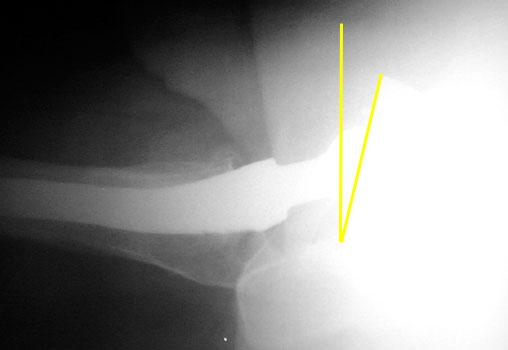

Femoral component should be anteverted. Exact degree of optimal anteversion is unknown

Femoral neck anteversion is difficult to accurately evaluate on radiographs, and can only be qualitatively assessed on a groin lateral view. This view is difficult to obtain, especially in the elderly or post operative patient, and is effected by pelvic or thigh rotation.

CT is the imaging modality of choice to evaluate for femoral neck anteversion.

Femoral neck anteversion on groin lateral film.